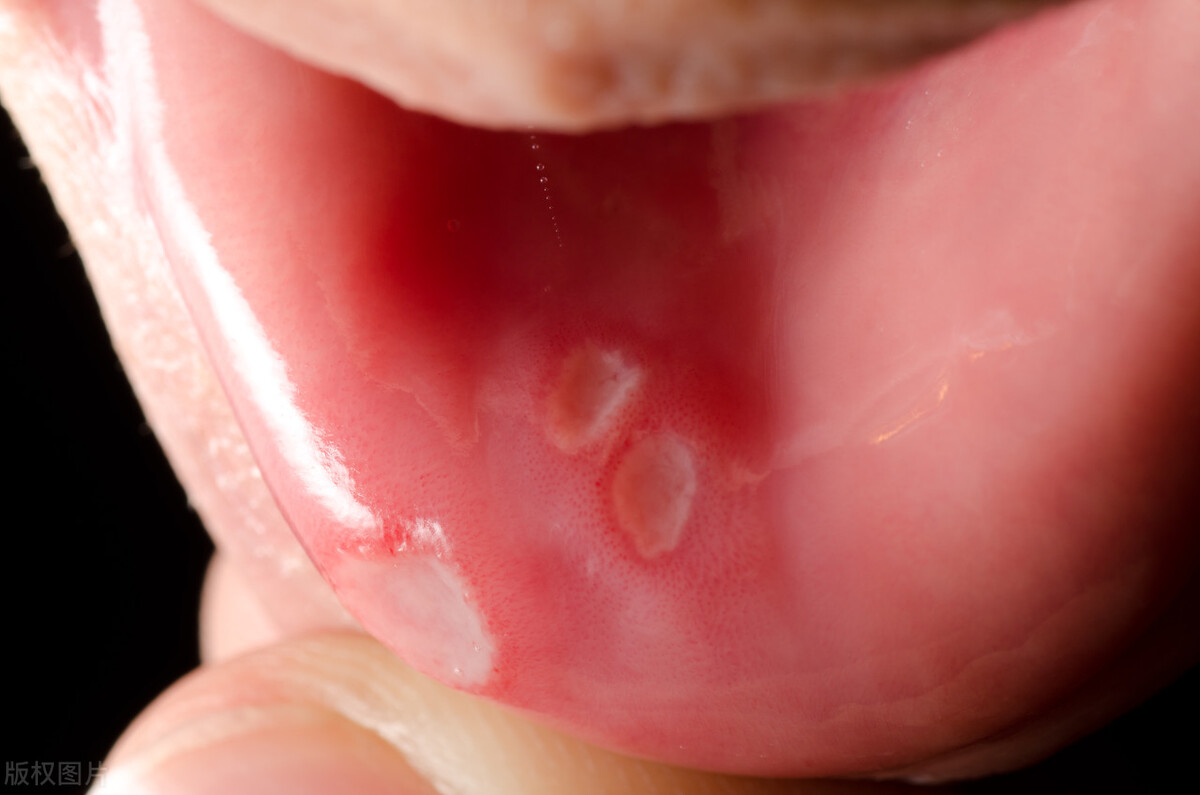

口腔溃疡是一种口腔黏膜病变,常常出现在口腔软组织的黏膜表面,例如口腔内侧、唇部、舌头、牙龈等处。口腔溃疡是常见的口腔疾病之一,全球范围内都有发生。口腔溃疡的病因不明确,可能与遗传因素、压力、感染、营养不良、免疫功能低下等多种因素有关。

单纯性口腔溃疡是最常见的类型,病程一般为7-10天,溃疡周围有红色边缘,溃疡本身为黄白色,通常大小不超过1厘米。复发性口腔溃疡是指口腔溃疡反复发作,持续时间长,治疗难度大。